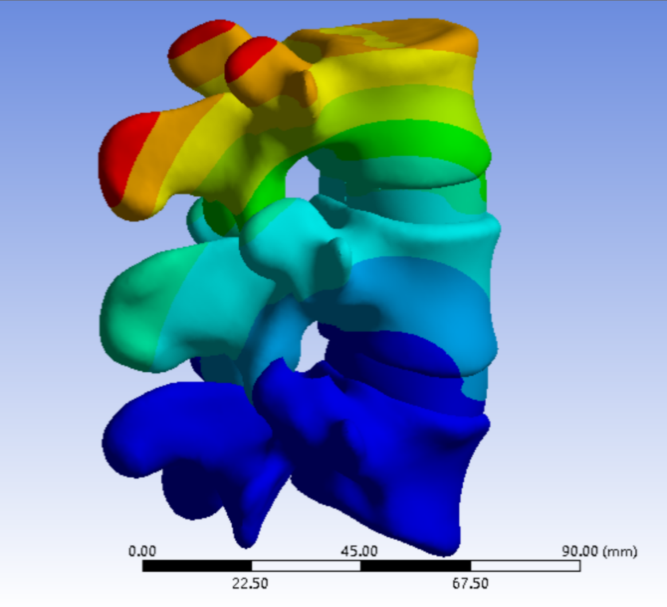

为解决以上问题���,我们提出“椎间孔镜按需成型5级法”��,即将椎间孔镜术中椎间孔成型的实际操作范围进行分级���:0级����:不成型����,见图 1��;1级���:软组织成型�����,只去除关节囊等部分软组织�����,基本不做骨性成型���,见图 2���;2级�����:少许骨质成型���,但不显露下关节突关节面����,见图 3����。3级成型�����:上关节突尖部或上1/2去除成型���,显露下关节突关节面���,见图 4�����;4级成型����:上关节突大部分成型或伴有部分椎弓����、峡部或下关节突小部分���,但预留基底部一部分��,见图 5��。

图 3 2级成型 |

2���、建立五级成型的有限元模型

正常腰椎模型命名为M0���;0级成型为M1��:不做骨性成型���;1级成型为M2���:软组织成型����,只去除关节囊等部分软组织���,基本不做骨性成型��;2级成型为M3����:少许骨质成型��,不显露下关节突关节面����;3级成型为M4a与M4b���:上关节突尖部(M4a)或上1/2(M4b)去除成型���,显露下关节突关节面����;4级成型为M5�����:上关节突大部分成型或伴有部分椎弓���、峡部或下关节突小部分�����,但预留基底部一部分���,见图16-20���。每组模型都按照前屈����、后伸���、左屈����、右屈���、左旋及右旋6种状态加载��,其他约束条件不变���,观察各组成型对于腰椎活动度及椎间盘应力的影响���。

图 17 2级成型 |